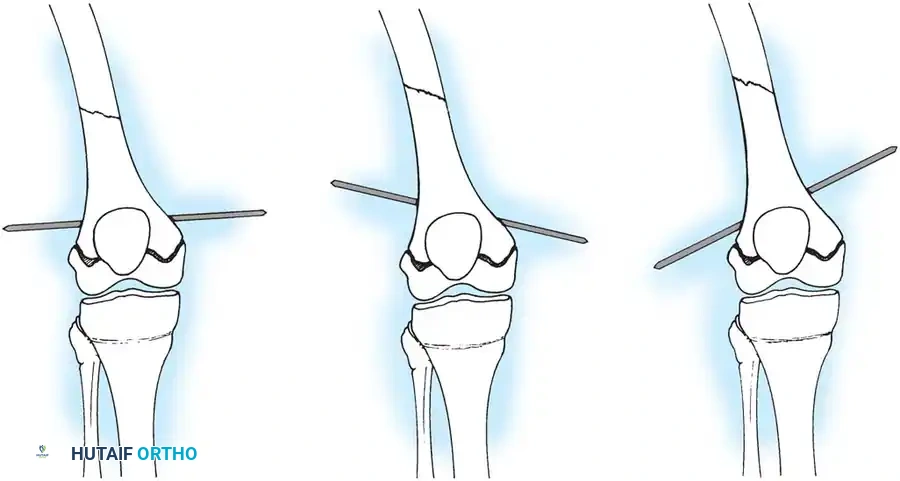

Biomechanical principles of Elastic Stable Intramedullary Nailing (ESIN), demonstrating the three-point cortical contact required for stability.

Intraoperative fluoroscopy demonstrating the retrograde insertion of elastic nails through the distal femoral metaphysis.

Surgical Technique:

1. Nail Selection: The diameter of each nail should be 40% of the narrowest diaphyseal medullary canal diameter. The combined diameter of both nails should fill 80% of the canal.

2. Entry Points: Medial and lateral incisions are made 2.5 cm proximal to the distal femoral physis.

3. Insertion: The nails are pre-bent to an apex that will sit exactly at the fracture site. They are advanced sequentially to the fracture.

4. Reduction and Crossing: The fracture is reduced closed. The nails are advanced across the fracture into the proximal metaphysis. Crucially, the nails must cross above or below the fracture site, never exactly at the fracture level, to maintain stability.

5. Final Seating: The nails are driven into the proximal femoral metaphysis, with the lateral nail terminating near the greater trochanter and the medial nail near the lesser trochanter.

Fluoroscopic view showing the elastic nails crossing in the diaphysis, ensuring symmetric construct rigidity.

Final seating of the elastic nails in the proximal femur. Note the divergent tips anchoring in the cancellous bone of the metaphysis.